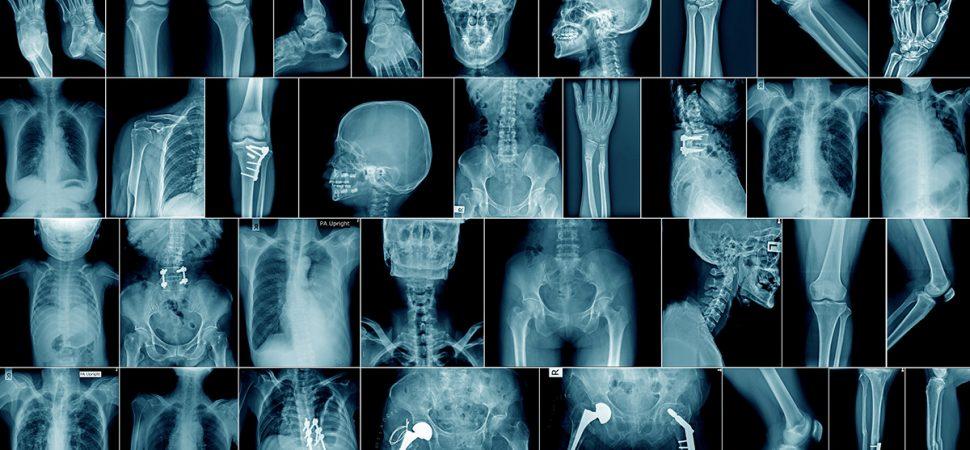

رادیولوژی و انواع آن

رادیولوژی، انواع و کاربرد آن ،رادیولوژی به مجموعه ای از روش های تصویربرداری از قسمت های داخلی بدن اطلاق می شود.

در رادیولوژی از اشعه ایکس با دوز پایین، امواج صوتی و یا میدان مغناطیسی برای تصویربرداری استفاده می شود.